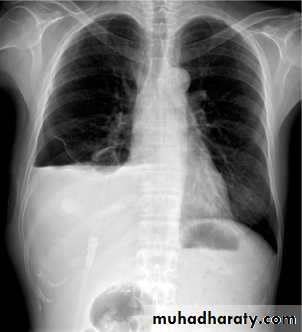

Chest imaging -2Pleural effusionPleural effusion tends to be used as a catch-all term denoting a collection of fluid within the pleural space. This can be further divided into exudates and transudates depending on the biochemical analysis of aspirated pleural fluid. Essentially it represents any pathological process which overwhelms the pleura's ability to reabsorb fluid.

Chest radiographs are the most commonly used examination to assess for presence of a pleural effusion, however it should be noted that on a routine erect chest x-ray as much as 250-600 ml of fluid is required before it becomes evident 6. A lateral decubitus film is most sensitive, able to identify even a small amount of fluid. At the other extreme, supine films can mask large quantities of fluid.

Both PA and AP erect films are insensitive to small amounts of fluid. Features include:

blunting of the costophrenic angle

blunting of the cardiophrenic angle

fluid within the horizontal or oblique fissures

eventually a meniscus will be seen, on frontal films seen laterally and gently sloping medially

A subpulmonic effusion (infrapulmonary effusion) may be seen when there is previously established pulmonary disease, but can also be encountered in normal lungs , They are more common on the right, and usually unilateral

with large volume effusions, mediastinal shift occurs away from the effusion (note: if coexistent collapse dominates then mediastinal shift may occur towards the effusion)